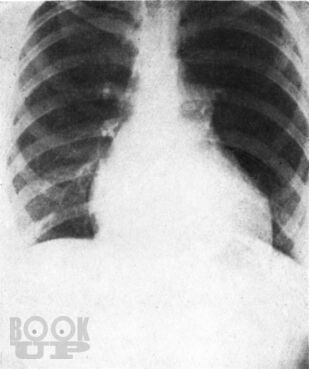

Монография всемирно известного автора посвящена вопросам клинической диагностики заболеваний сердца. Детально освещены общее исследование больного, сбор анамнеза и анализ жалоб, оценка симптомов, полученных при физикальном обследовании, а также при использовании рентгенологического и электрокардиографического методов. Для каждого заболевания автор выделяет решающие симптомы-“ключи”, помогающие установить точный диагноз.